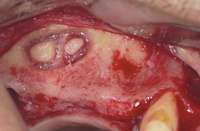

Figure 1A through Figure 1C Buccal and radiographic views of posterior edentulism with significant sinus pneumatization in the molar region.

Figure 1D Lateral wall osteotomy.

Figure 1E The osteotomy was grafted with particulate bone. Figure 1F The surgical site was covered with a resorbable barrier.

Figure 1G Radiographic confirmation of bone regeneration 8 months after surgery. Figure 1H Radiographic confirmation of implant osteointegration into the new bone 14 months after the initial surgery. Figure 1I. Final implant-supported restoration.